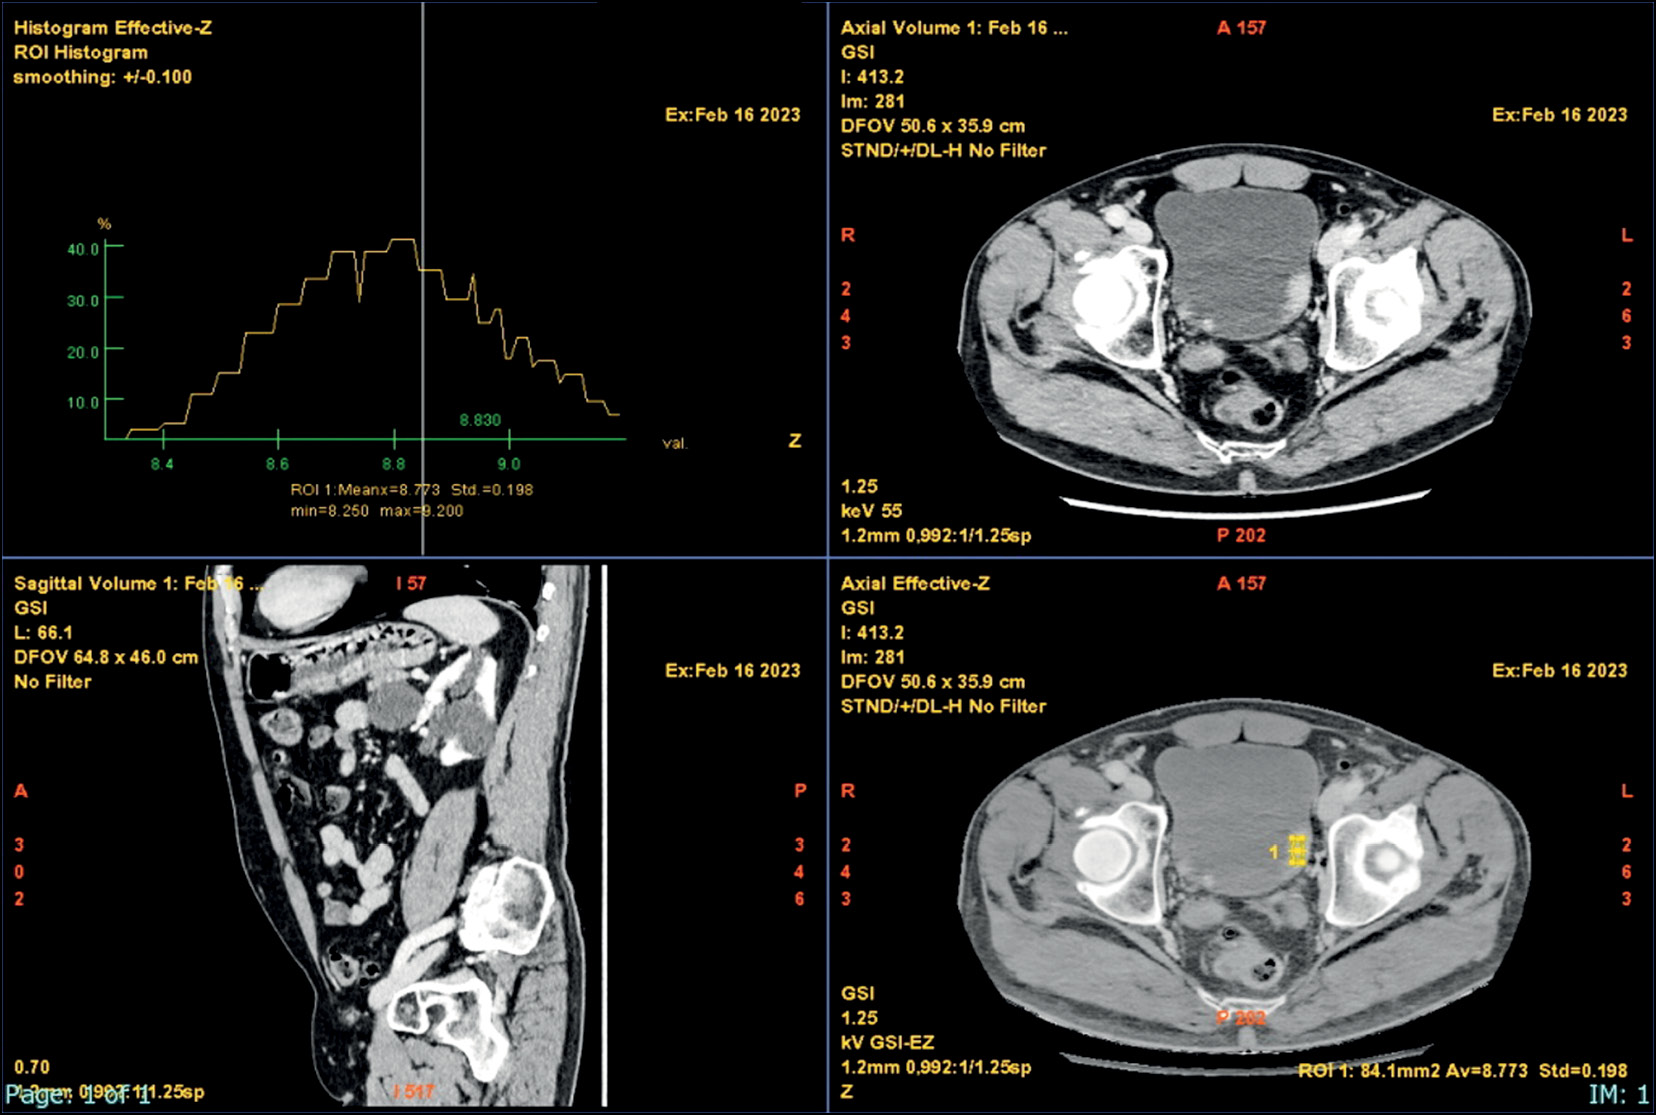

Атомная карта (Zeff)

Карта фактических зарядовых чисел применяется для количественной оценки различий материалов и измерения различий в затухании в зависимости от уровня энергии (рис. 3) [34].

Рис. 3. Атомная карта (Zeff) с гистограммой.